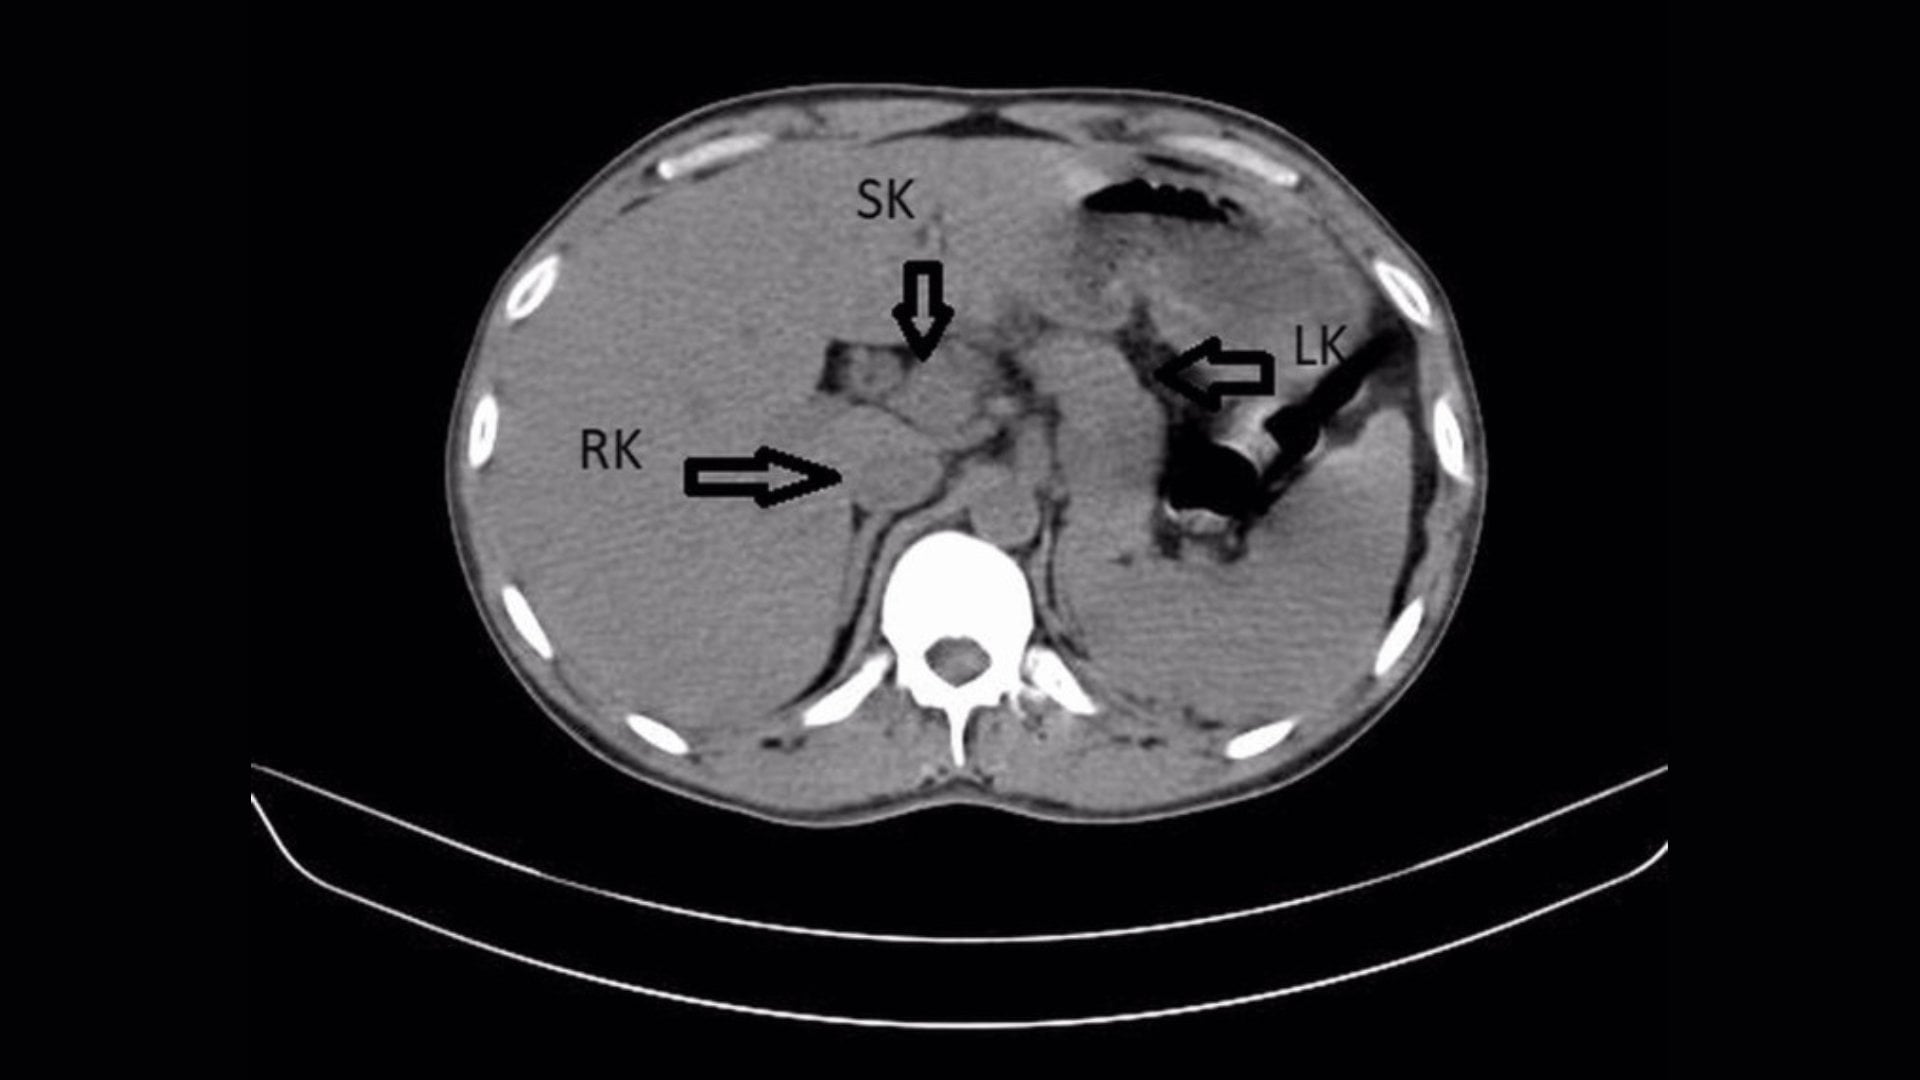

Sıradan bir bel ağrısıyla hastaneye gidip üç böbreğiniz olduğunu öğrenmek epey tuhaf olmalı. Anne karnında böbrekleri oluşturan dokunun beklenmedik şekilde fazladan bölünmesi buna yol açıyor. İşin ilginç yanı, bu gizli organların genelde kusursuz çalışması. Çoğu insan, basit bir taş veya enfeksiyon geçirene dek bunu fark etmiyor. Bu hücresel sapmayı tam olarak neyin tetiklediğini hala bilmiyoruz. Bedenimizin bizden habersiz yedek parça üretip saklayabilmesi çok acayip.